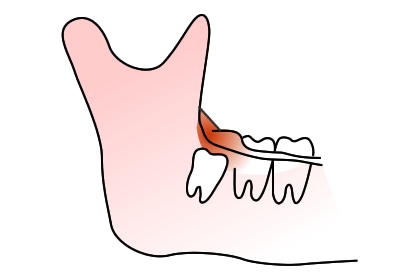

親知らずを抜かなくてはいけないのか、悩んでる方は多いと思います。親知らずを放っておくと次のようなトラブルを起こす可能性があります。

親知らずが傾斜して前の歯に引っかかっているケースは、前の歯が虫歯になりやすいので、症状が無くても早期に抜歯した方が良いことがあります。

上の写真のケースでは、親知らずが横を向いて前の歯との間に食渣が非常に挟まりやすい状態になっていました。患者さんご本人も気になっていましたが放置されていたため、左下の歯が痛くなり、来院された時には親知らずの前の歯が神経に達するほどのむし歯になっていました。

ここが虫歯になると、神経に近接しているため治療が困難になり、神経の治療を行っても予後が悪くなります。